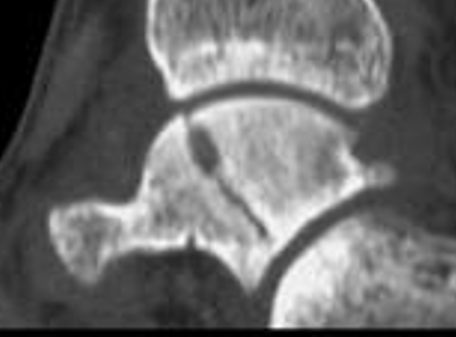

Xray / CT

Ensure no displacement / malalignment

Xrays

| AP | Lateral | Canale View |

|---|---|---|

| Entry point of the screws |

Evaluate neck reduction

|

Evaluates the neck reduction |

Lateral off articular surface Medial through articular cartilage |

Depth of screws |

Beam angled 75o to foot Foot 15o pronated |